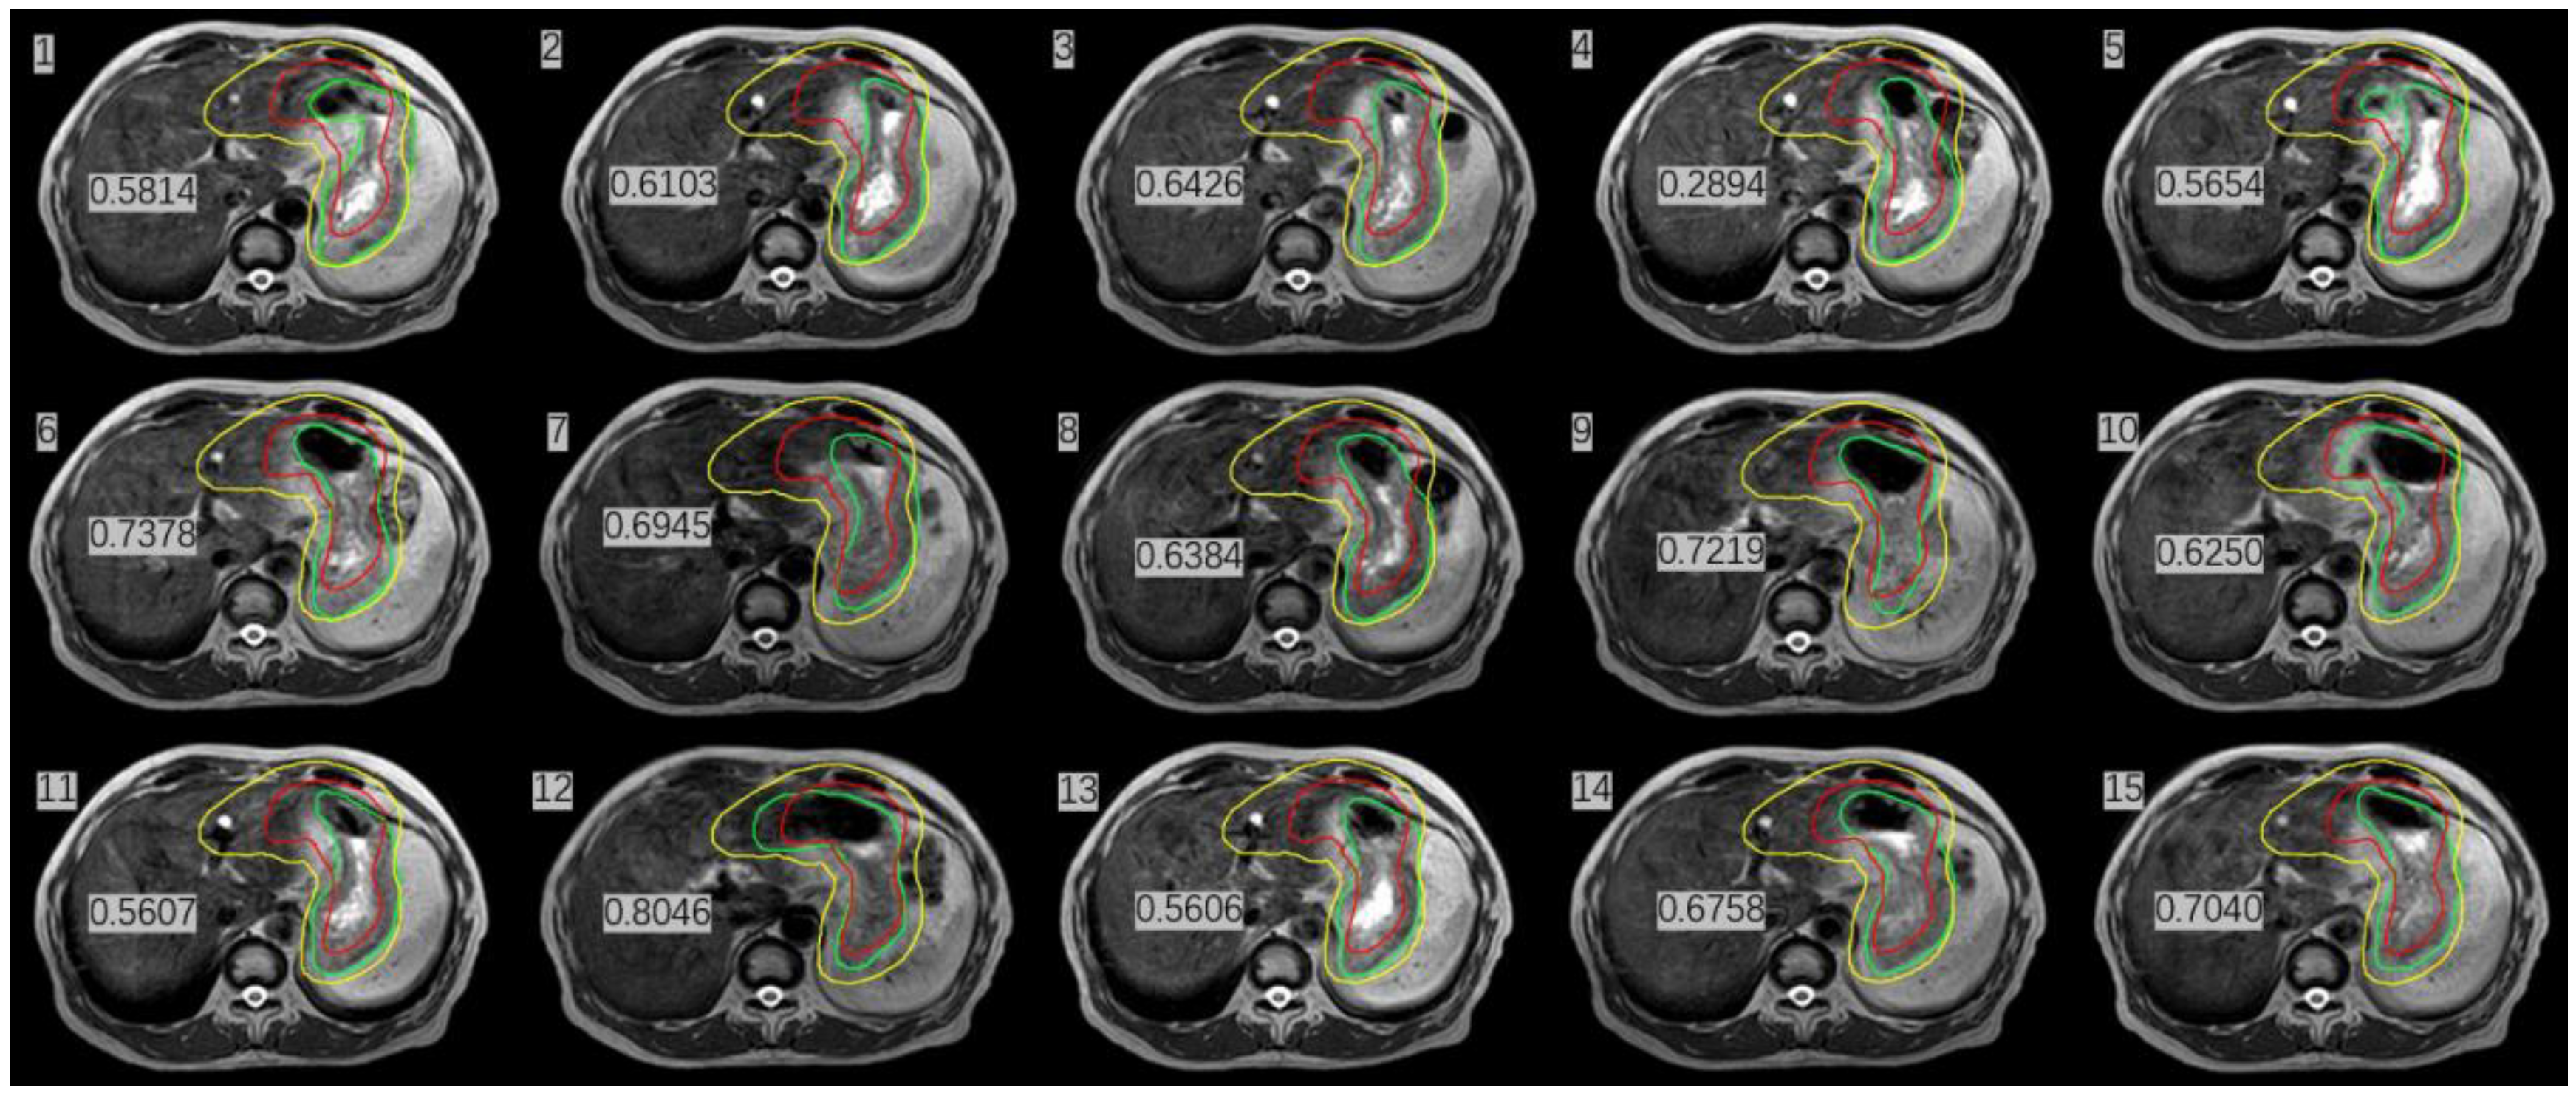

A 53-year-old male patient with a history of gastric bleeding and gastric ulcer for more than 18 years was selected for this study. The patient developed melena on 13 January 2022, without obvious causes. Contrast CT of the chest, abdomen, and pelvis showed that the wall of the gastric antrum was thick with two enlarged lymph nodes. Fluorodeoxyglucose positron emission tomography/CT (FDG-PET/CT) images revealed high FDG uptake in both the gastric wall of the inhomogeneously thickened greater curvature and the two enlarged lymph nodes. Pathological reports presented mucosa-associated lymphoid tissue (MALT) lymphoma in the greater curvature at the junction of the astral body, after performing immunohistochemistry of CD20+, CD43+, CD3+, BCL2+, CD5 minority+, CD23 minority-, CD38 minority+, CyclinD1 minority+, Lambda individual+, BCL-6-, Kappa-, Ki-67+10%. The patient was diagnosed with stage IIE gastric MALT lymphoma according to Ann Arbor staging. The patient received four cycles of rituximab, 600 mg, and then involved site radiation therapy (ISRT) on the whole stomach. The patient underwent a 4D CT scan on an empty stomach. Before the CT simulation, anisodamine (dose, 10 mg) was administered to reduce gastric motility. The entire stomach (clinic target volume, CTV) was delineated in the 4D CT scans, and the images were combined into an internal CTV (iCTV). The combined iCTV included the enlarged metastatic lymph nodes and the planning target volume (PTV), which presented a 5 mm external expansion from iCTV. The patient was treated with ISRT at 30 Gy in 15 fractions. Then, the patient was treated with the Unity MR-LINAC. Prior to each radiotherapy fraction, the patient was kept on an empty stomach and was administered anisodamine (dose of 10 mg). The empty stomach was delineated with automated segmentation using the AI technique, and then the resulting image was reviewed and modified by an attending radiation oncologist. The MRI image of the whole stomach after anisodamine administration was clearer than the images taken without administering the drug (Figure 1). The images obtained with the AI technology using deep learning algorithms showed that the delineation accuracy of the whole stomach gradually improved. The Dice similarity coefficient (DSC) increased gradually (Figure 2). The DSC measures the volumetric overlap of two sets of data and was obtained with the following Equation (1), which calculates the quotient of similarity between two volumetric sets with a value between 0 and 1. In this formula (Equation (1)), A and B are the target area volumes obtained by AI and manually corrected, respectively. A DSC of 1 means perfect segmentation, whereas a DSC of 0 means no overlap at all.

Figure 2.

Comparison of images of the whole stomach on the same plane after the 1st, 5th, 10th, and 15th fractions, showing the radiation oncologist’s delineation (red line) and the delineation obtained with AI (orange line). The dice similarity coefficient (DSC) of the three-dimensional stomach images indicated by these four outlines are 0.8311 (a), 0.9185 (b), 0.9193 (c), and 0.9427 (d), respectively.

We calculated the DSC after stomach delineation of real-time MR imaging and simulation CT imaging. Interestingly, we found that the patient’s inter-fractional stomach variation changed greatly. With CBCT online guidance, even after expanding the PTV by 1 cm as usual, there remain 8/15 axis planes that could not cover the entire stomach; therefore, the target, i.e., the entire stomach, would be missed (Figure 4) At the same time, we could monitor the organs around the stomach, such as liver, left kidney, and spinal cord, which were irradiated daily, and compared their state them with that of the same organs after a mean dose in the CT simulation. (Table 1) The liver and duodenum were on average less exposed to toxic doses in each MRI-guided treatment than in the CT simulation (liver: 840.7 cGy < 929.1 cGy, duodenum: 874.9 cGy < 1025.1 cGy). Although the average doses received by the spinal cord and the left kidney were slightly higher in MRI-guided therapy than in CT simulation (spinal cord:483.3 cGy > 470.8 cGy, left kidney: 297.7 cGy > 277.7 cGy), they were far lower than their respective dose constraints (the maximum dose constraint for the spinal cord is 4500 cGy, and the average kidney dose constraint is less than 1800 cGy) [8].

Figure 4.

Stomach delineation DSC (number in Figure) of real-time MR imaging and simulation CT imaging the (red line delineates the stomach on the simulation images, the green line delineates the stomach on the daily MRI images, and the yellow line delineates the stomach considering 1 cm external expansion from the iCTV).

IGRT has become routine as a standard configuration in modern radiation therapy. Imaging the patient prior to treatment can help reduce the impact of setup errors, thus improving the dose delivery accuracy [13]. Currently, most modern radiotherapy systems are equipped with kV CBCT to visualize anatomical structures and identify the target volumes. Although CBCT is highly effective, it provides images with poor quality for soft tissues—including abdominal organs such as the liver, stomach, and pancreas—which makes it very difficult to accurately identify the soft-tissue targets and surrounding OARs. In the case of our gastric MALT lymphoma patient shown in Figure 5, it was not feasible to use CBCT for image guidance because of its poor image quality. A larger PTV margin with at least 1 cm had to be delineated, but this would cause higher toxicity to OARs. In addition, a 1 cm margin could not cover the entire empty stomach even if anisodamine (dose 10 mg) was administered to reduce gastric motility (Figure 4) [14] (pp. 174–177). As shown in Figure 4, even after expanding the PTV by 1 cm as usual with CBCT online guidance, there remain 8/15 axis planes that could not cover the entire stomach. Therefore, the target, i.e., the entire stomach, would be missed in regular clinical practice without MRI image guidance. Poor CBCT imaging of the stomach makes it more challenging to incorporate corrections for certain differences in routine patient anatomy, as well as to use approaches based on adaptive treatment protocols. The MR-LINAC system overcomes the limitations of traditional IGRT, especially for soft tissues requiring the precise definition of the target and of OARs. MR-LINAC improves IGRT by enhancing soft-tissue contrast in MR images without delivering concomitant radiation doses. MR-LINAC brings a unique emerging workflow that can help radiation therapy practitioners improve their skills and understand MR anatomy. The case reported here illustrates that MR-LINAC could visualize the stomach clearly, especially after administering anisodamine. Meanwhile, an attractive option for MR-LINAC might be to re-optimize or adjust the therapeutic plan before each radiation treatment. Diagnostic-quality MR images can be acquired based on the actual patient anatomy before and during treatment and then used in an online adaptive workflow. Compared to CBCT, online 1.5 T MRI provides better target visualization on an MR-LINAC and aids online adaptive treatment strategies, including daily replanning. Although online adaptation techniques guided by CBCT are improving, the quality of stomach images obtained by CBCT is likely to remain poor. In contrast, in MRI-guided therapy, increased soft-tissue contrast can more accurately visualize day-to-day variations and may allow the delineation of a smaller PTV margin, thus reducing OAR toxicity [15].

The main limitation of MRI-guided adaptive planning is the fact that it requires the delineation of the target volume including tumor and OAR daily, which is time-consuming for radiation oncologists. However, automated segmentation using AI is an effective way to the delineate target volume quickly. Our case showed that automated segmentation using AI deep learning could delineate the target volume more and more accurately and efficiently.